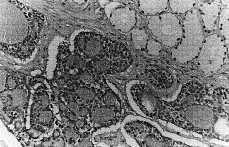

El estudio histopatológico mostró una tumoración constituida por proliferación de estructuras tubulares, con patrón cilindromatoso, tapizadas por dos capas de células de pequeño tamaño, uniformes y con material acelular en el interior de los espacios tubulares. Se observó clara invasión perineural. En el estudio inmunohistoquímico, las citoqueratinas fueron claramente positivas, de forma difusa en la capa interna, mientras que el antígeno de membrana epitelial fue positivo en los bordes luminales. Se observó además positividad focal para S-100 en las células mioepiteliales periféricas (Fig. 1).

Figura 1. Grupos de células tumorales con patrón cilindromatoso con material acelular intraluminal. (HE, *400.)